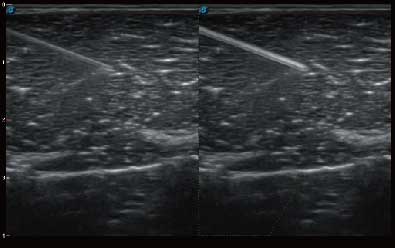

自动识别穿刺针进行声束智能偏转 手动修正多档调节 提高一次穿刺成功率

自动识别组织边界信息进行图像无损拼接 抖动抑制技术提高成像效果 完整显示较大病灶及组织,为临床提供可靠诊疗方案